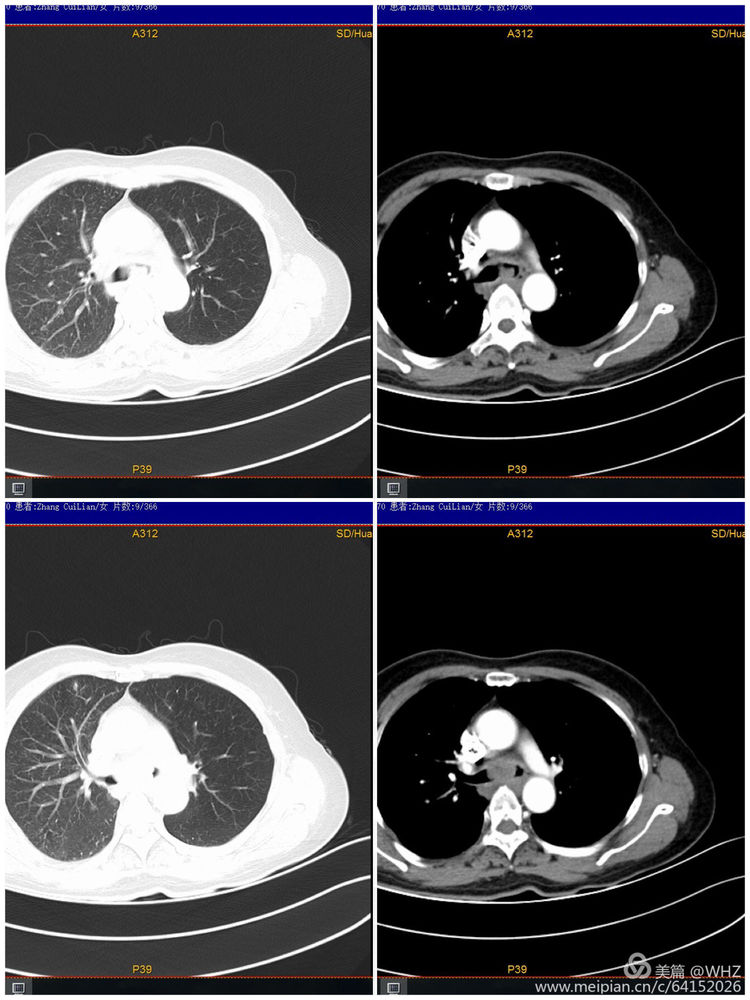

63岁的张女士,因咳嗽、喘憋了1个多月来院检查,查体显示双肺呼吸音粗,闻及吸气相哮鸣音。通过CT等检查诊断为肺部肿瘤,支气管镜检查发现左主支气管狭窄,如不及时处理随时会发生呼吸道梗阻而危及生命。

胸部CT示经气管镜活检病理为低分化腺癌伴灶性鳞状分化,基因监测无突变。

呼吸与危重症医学科和麻醉科经过认真的术前讨论和充分的准备,于8月2日为患者进行气管镜下APC(氩等离子体凝固)肿瘤切除术。术中发现左主支气管新生物浸润样生长,管腔不完全阻塞,仅剩15%左右,予以APC烧灼肿瘤后管腔增宽至80%,右主支开口处粘膜受累,管腔不完全阻塞,予以APC烧灼肿瘤组织。手术顺利,术后患者胸闷、喘憋明显减轻,吸气相哮鸣音消失。目前已顺利出院。